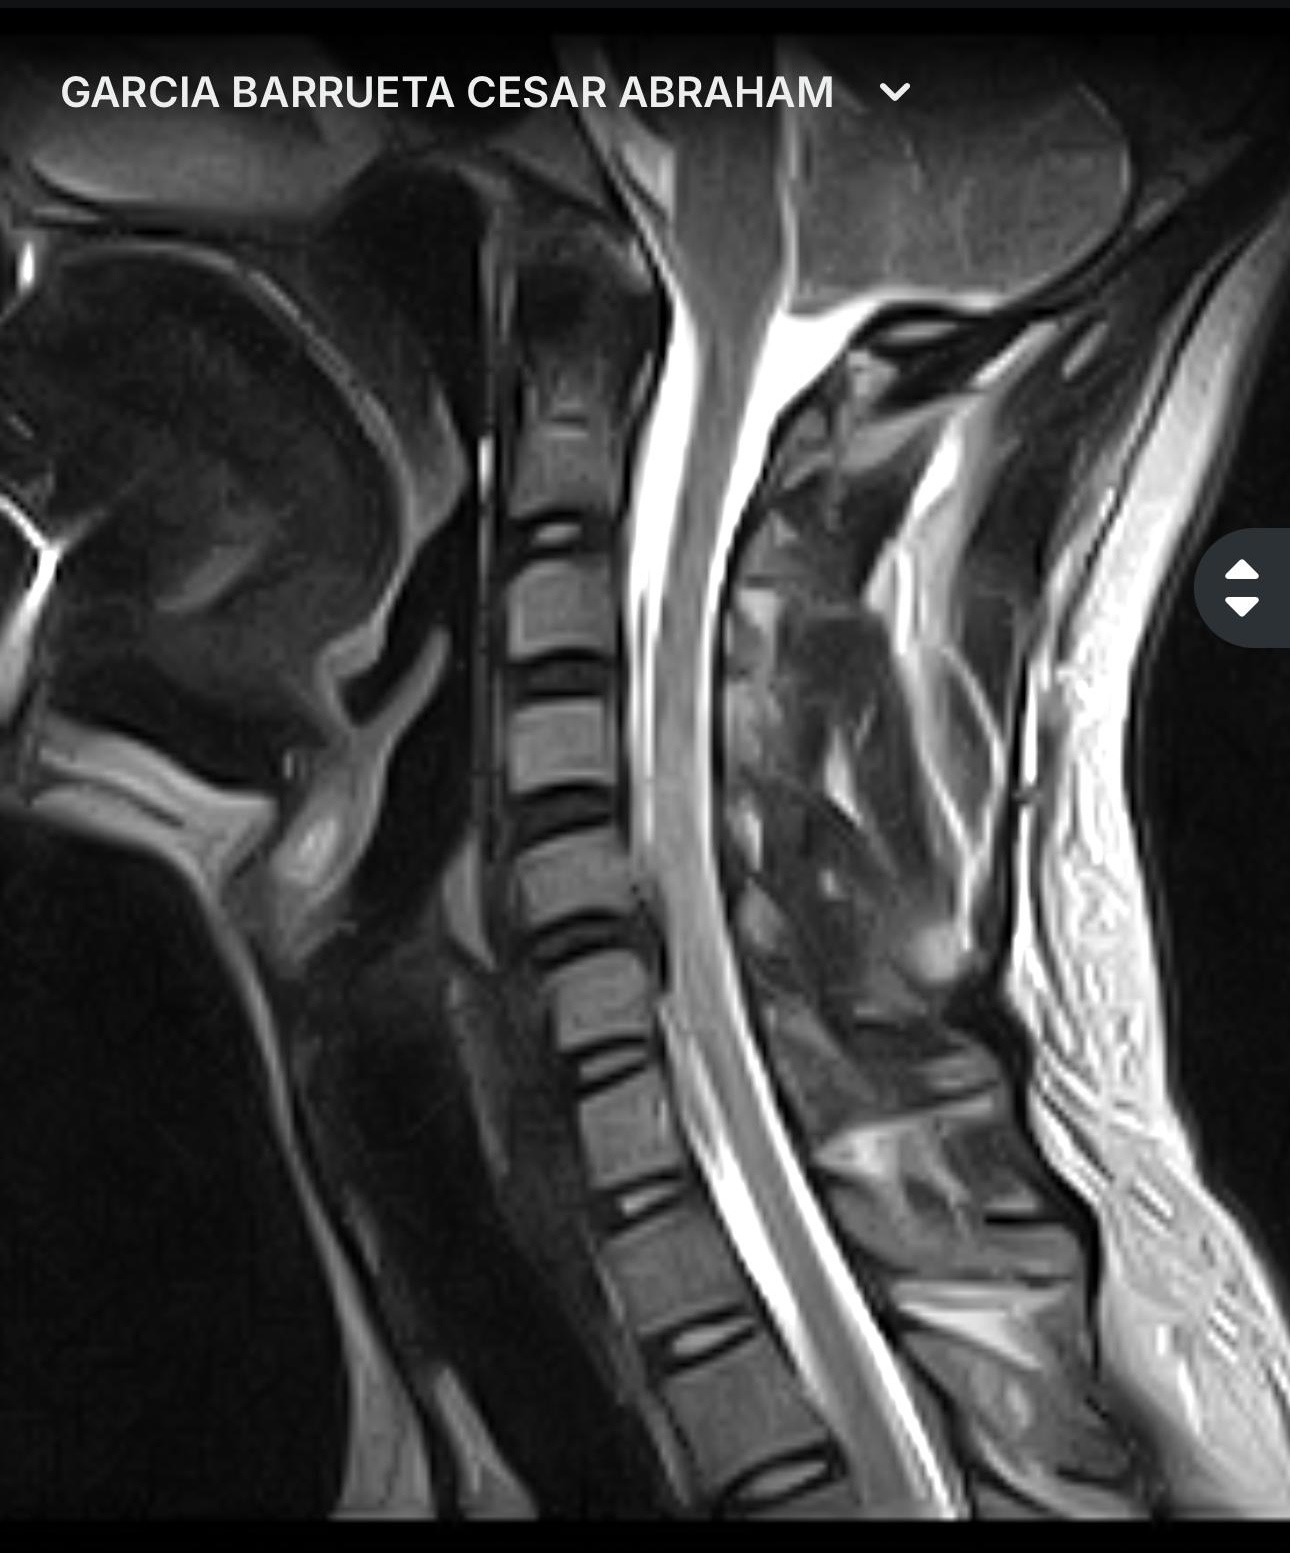

El dolor en el hombro no se calmo, el entumecimiento sigue actualmente en mi brazo izquierdo hacia el dedo pulgar, por lo que me realice una RM donde un neurólogo clínico y el neurocirujano especialista en columna, me diagnosticaron una protrusion discal en C6 con migración hacia abajo, que comprime el cordón medular, el agujero de conjunción derecho estrecho en C5 C5 lo que significa una subluxación facetaria, afortunadamente no pasó a mayores y sigo con movilidad en todos los miembros, pero tengo problemas de sensibilidad en el brazo izquierdo. Por eso requiero de esta cirugía de extirpación del disco intervertebral con estabilización espinal para corregir la subluxación.